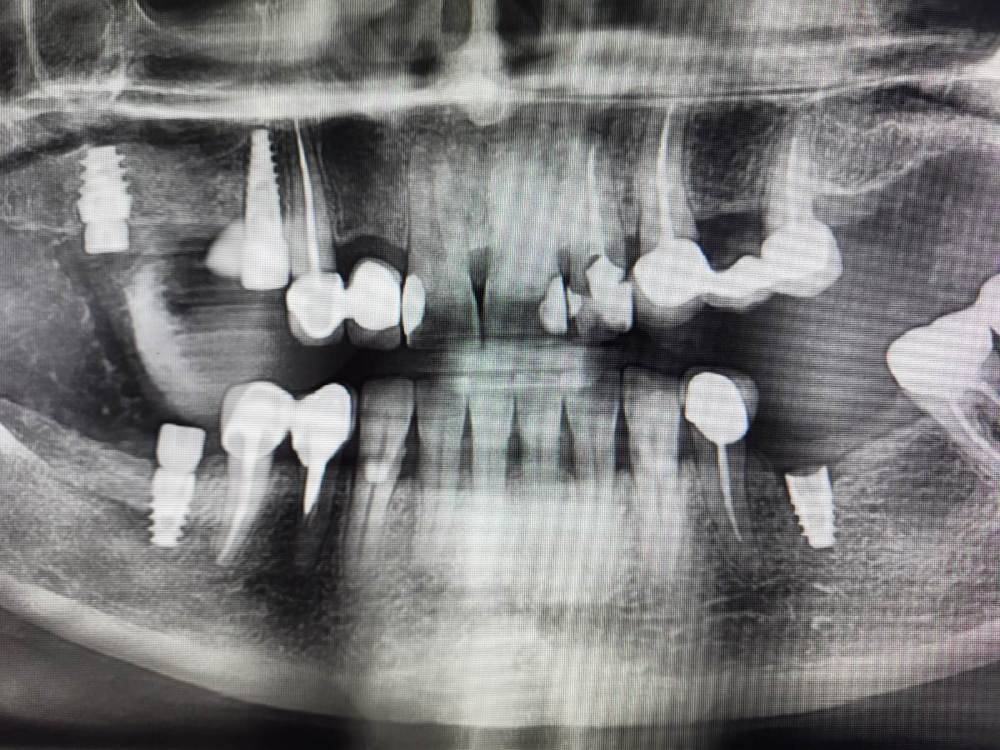

Irouil Опубликовано 28 ноября, 2023 Поделиться Опубликовано 28 ноября, 2023 Дорогие коллеги, прошу советов и мнений Пациентка 52 лет, соматика без особенностей В мае 2023 установлен имплант в позицию 3.5, первый срез КТ - на момент установки. В августе был утерян ФДМ, установил другой, снимок на момент обращения с незначительной резорбцией В ноябре пациентка пришла протезироваться, у винта выраженная щелевидная резорбция язычно и кратерообразная - параплатформенно Три других винта, установленных в то же время (но без головняка с ФДМ) выглядят более чем удовлетворительно Что скажете? P.S. поперечный срез КТ выставлен на уровне платформы импланта Ссылка на комментарий